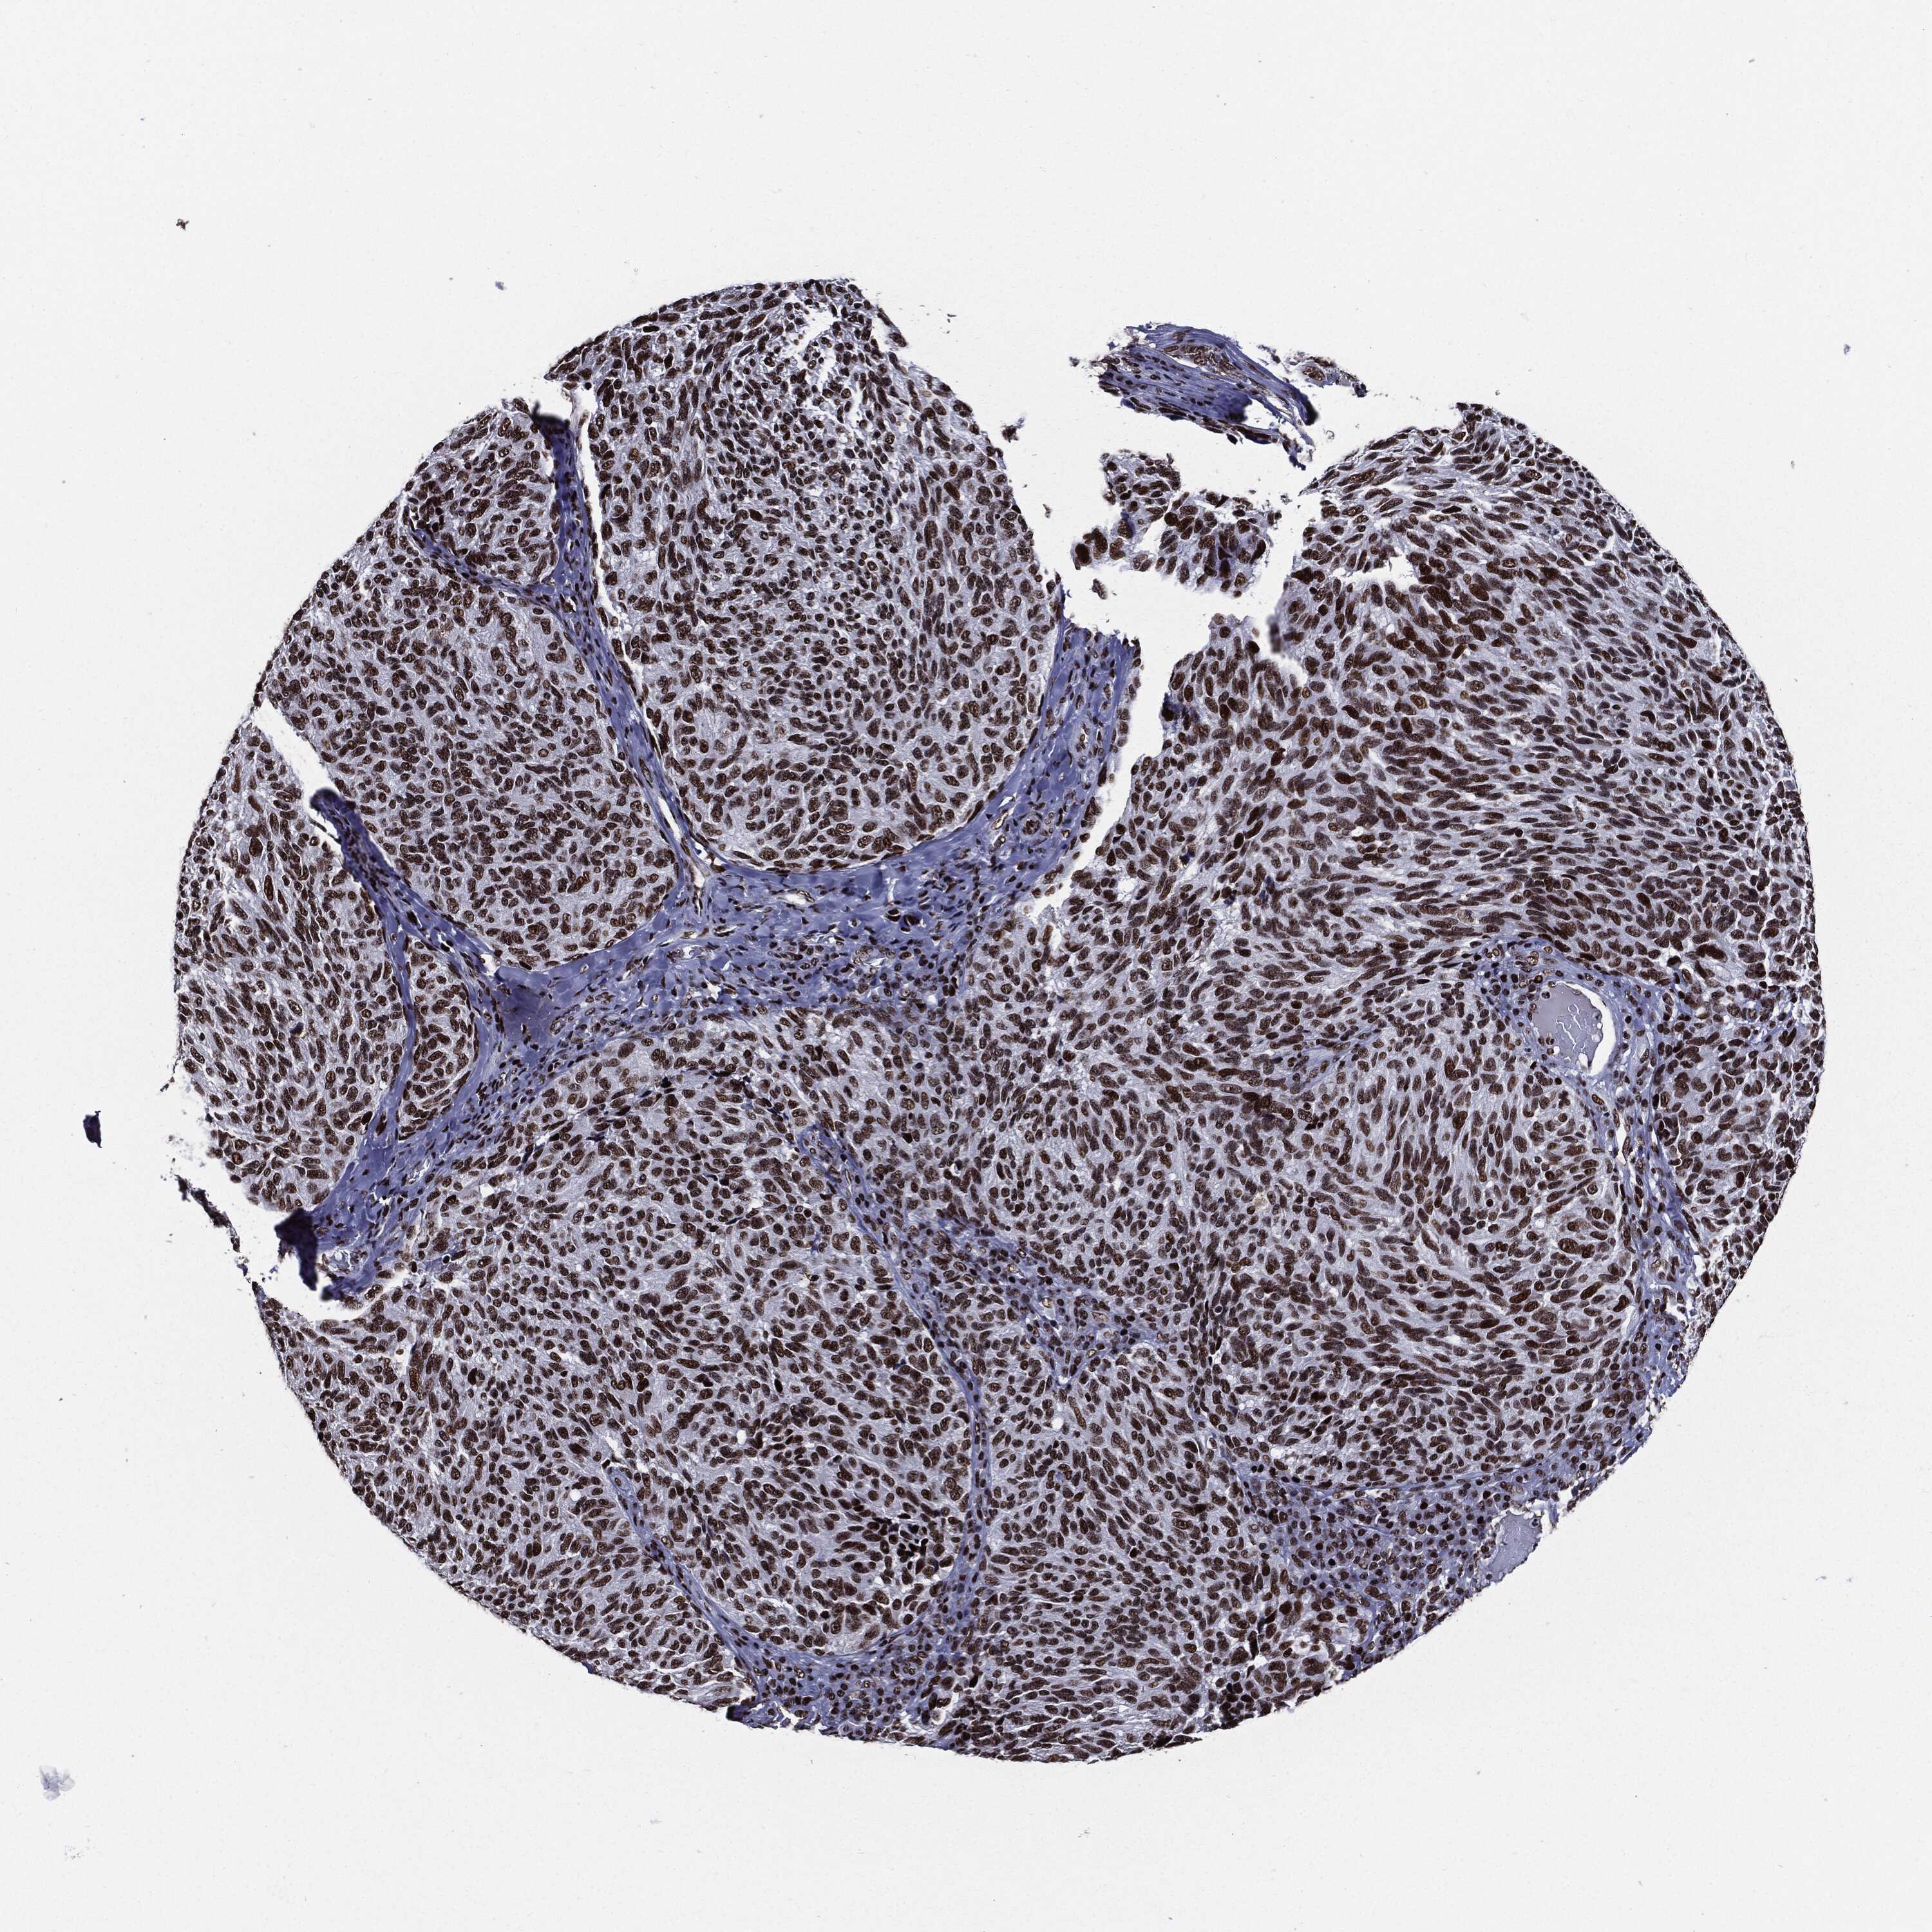

MELANOMA - Protein expressioni

A mouse-over function shows sample information and annotation data. Click on an image to view it in a full screen mode. Samples can be filtered based on level of antibody staining by selecting one or several of the following categories: high, medium, low and not detected. The assay and annotation is described here.

Note that samples used for immunohistochemistry by the Human Protein Atlas do not correspond to samples in the TCGA dataset.

Antibody stainingi

Antibody staining in the annotated cell types in the current human tissue is reported as not detected, low, medium, or high, based on conventional immunohistochemistry profiling in selected tissues. This score is based on the combination of the staining intensity and fraction of stained cells.

Each image is clickable and will lead to virtual microscopy that enables deeper exploration of all samples and also displays staining intensity scores, fraction scores and subcellular localization as well as patient and tissue information for each sample.

Antibody HPA024037

Antibody HPA065325

Antibody HPA074591

Antibody CAB025417

Staining

High

Medium

Low

Not detected

Intensity

Strong

Moderate

Weak

Negative

Quantity

>75%

75%-25%

<25%

None

Location

Nuclear

Cytoplasmic/membranous

Cytoplasmic/membranous,nuclear

Malignant melanoma, NOS

Malignant melanoma, Metastatic site